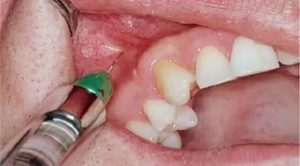

Травматический периостит — нередкое явление после экстракции зуба. Его лечение производят по следующей схеме:

- Проводят местную анестезию для обезболивания участка операции.

- Разрезают десну в пораженном месте.

- Удаляют гнойные массы и очищают костную ткань.

- Обрабатывают рану антисептиками и устанавливают дренаж.

- Проводят лечение соседних зубов.